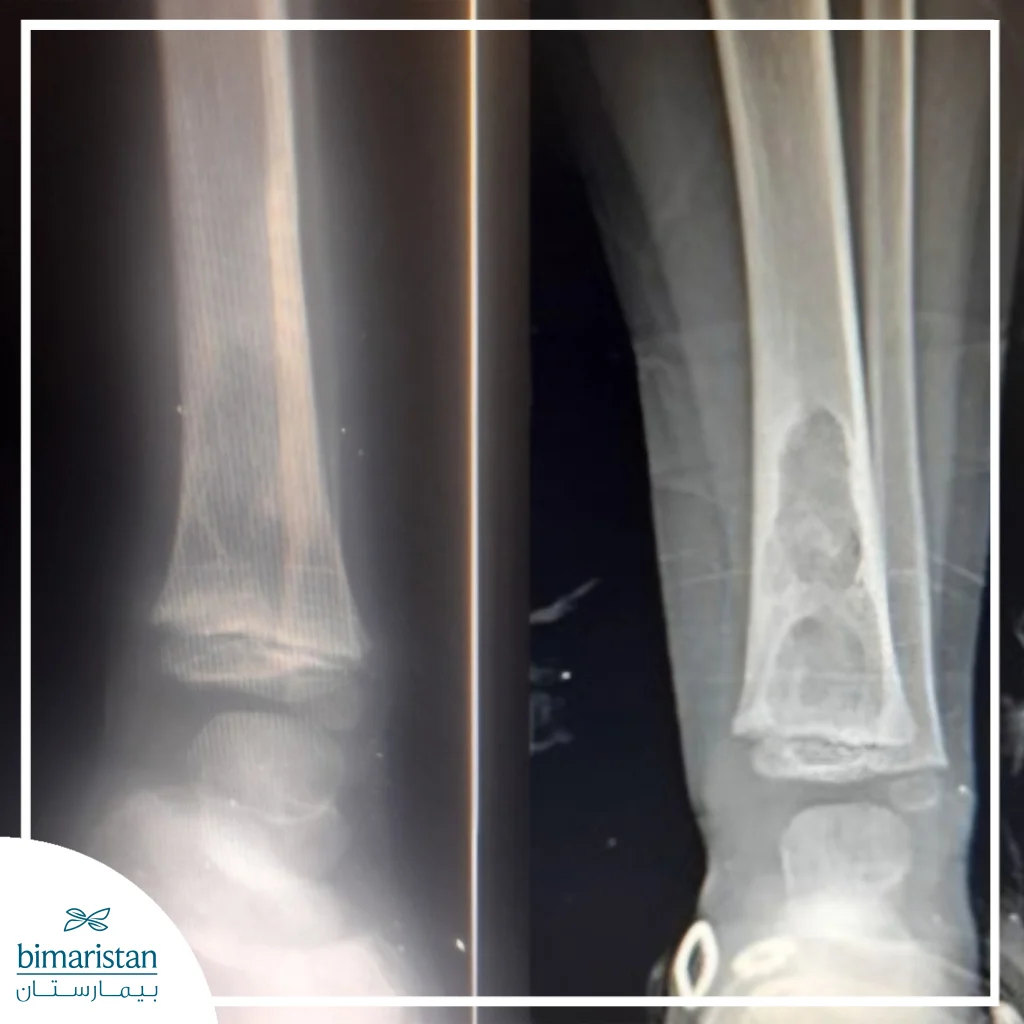

2. Bone or joint tuberculosis

Bone TB is the second most common form of extrapulmonary tuberculosis and occurs when the germ reaches the bones or joints through the bloodstream from a previous pulmonary focus. The disease usually affects the spine in the thoracic or lumbar vertebrae, and this form is known as Pott’s disease. The infection begins with chronic pain in the back or affected joint that gradually increases over time, and the patient may notice stiffness in movement or swelling in the area. As the condition worsens, spinal deformity or compression of the spinal nerves may occur, leading to weakness or paralysis in the lower limbs.

In the joints, the disease manifests as a chronic, slowly progressive inflammation that often affects the hip or knee joint, causing intermittent pain and mild swelling that increases with movement. This form of tuberculosis is characterized by a long course and unclear symptoms at the beginning, and is often diagnosed months after the onset of symptoms due to the absence of characteristic signs in the early stages.